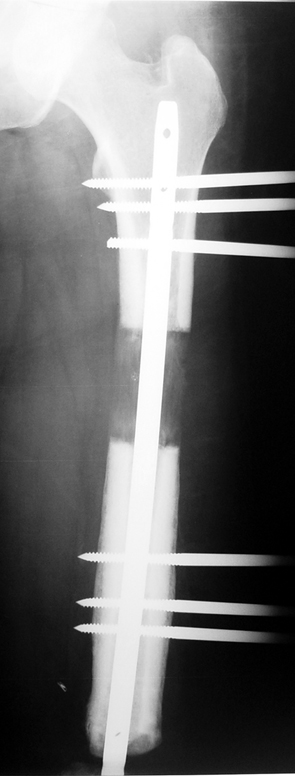

Vaka 3